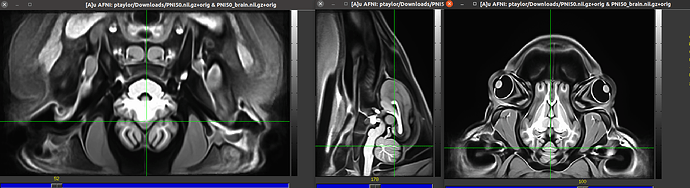

I am currently trying to use @animal_warper to align a dataset to a template, save the warp and inverse warp, apply those transforms to follower datasets like atlases, segmentations, and masks, and do skull stripping by warping a template brain mask back to native space. I looked at both the datasets in ITK snap and both the native and template centers are way apart. So I used itksnap to clisely register them to have the same center as the template space and use animal warper. But everytime i run following code, I get the following error. Could some please shine light on why this is happening. I perfromed this before brining the centers of both the datasets close and wide apart.